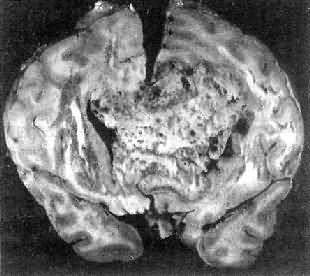

肉眼观,肿为数厘米的结节至巨大块状。分化较好的肿,境界不清;而分化程度较低的肿则境界分明。体灰白色。质地视肿内胶质纤维多少而异,或硬、或软、或呈胶冻状外观,并可形成大小不等的囊腔。由于肿的生长、占位和邻近脑细胞的肿胀,脑的原有结构因受挤压而扭曲变形(图16-23)。

图16-23 星形胶质细胞

左大脑半球肿胀,肿边界不清,部分呈胶冻状

高度恶性的星形胶质细胞称为多形性胶质母细胞(glioblastoma multiforme),多见于成人。肿好发于额叶、颞叶白质,浸润范围广,常可穿过胼胝体到对侧,呈蝴蝶状生长(图16-24)。体因常有出血坏死而呈红褐色。镜下,细胞密集,异型性明显,可见怪异的单核或多核巨细胞。出血坏死明显,是其区别于间变性星形胶质细胞的特征。毛细血管明显增生,内皮细胞增生、肿大,可导致管腔闭塞和血栓形成。肿发展迅速,预后极差,患者多在2年内死亡。

图16-24 多形性胶质母细胞

在两半球内肿呈蝴蝶状,边界不清,切面见有出血、坏死及液化